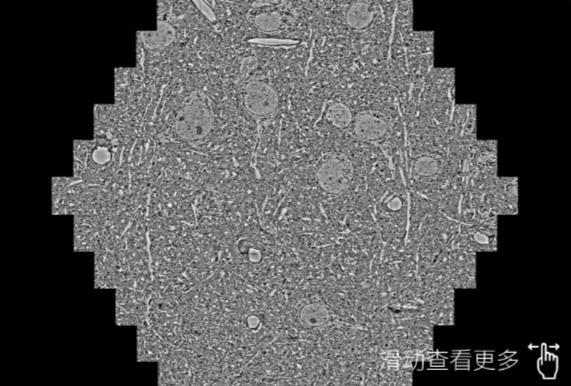

鼠脑切片。左图使用湖州蔡司湖州扫描电镜MultiSEM706对165μmx143pm面积区域成像,耗时仅需1.5秒。右图为鼠脑切片中30μm区域放大效果。样品由芝加哥大学B.Kasthuri提供。

使用蔡司高速湖州扫描电镜MultiSEM对1mm²人脑皮层组织进行高分辨成像,并对其中的各种细胞结构进行三维重构分析。左图展示了2x3mm²组织平面中锥体神经元的三维重构效果。右图显示了局部体积神经元三维重构。图像由哈佛大学chtman实验室提供,渲染图由D. Berger 制作。